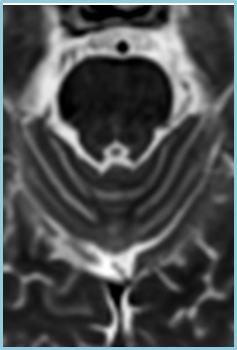

在磁共振领域,深度学习技术对图像进行降噪、上采样、减轻振铃伪影的处理,带来了清晰且细节丰富的图像。

过去,高分辨率图像的获取往往伴随着漫长的扫描时间,这影响了图像获取的效率,对于危重疾病的快速诊断是一大挑战。然而,PIQE技术的出现彻底颠覆了这一局面。此次发布的全新3T磁共振Galan Supreme,搭载全新的自研磁体和梯度线圈,并深度融合PIQE技术,可以实现在不增加扫描时间的前提下,轻松获取到高分辨率的图像,为临床带来了兼具高效与高质量的影像体验。

左右滑动查看更多